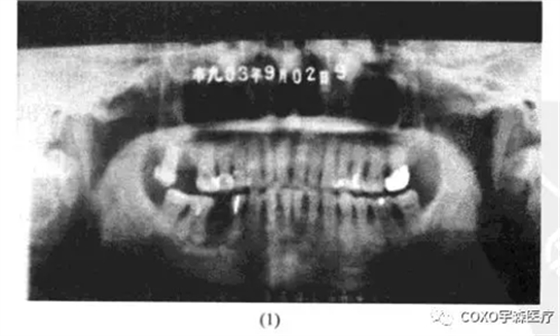

病例: 男性,71歲,雙側(cè)下頜骨后牙區(qū)反復(fù)腫脹2年余,曾在當(dāng)?shù)蒯t(yī)院口腔科行5]根管治療術(shù),效果不明顯,而將5]拔除,拔牙創(chuàng)一直未愈并伴疼痛,故轉(zhuǎn)我院就診。

x線片示:雙側(cè)后牙區(qū)高密度陰影(圖13-7),初步診斷:雙側(cè)后牙區(qū)根尖周骨質(zhì)結(jié)構(gòu)異常,伴感染,收入院。